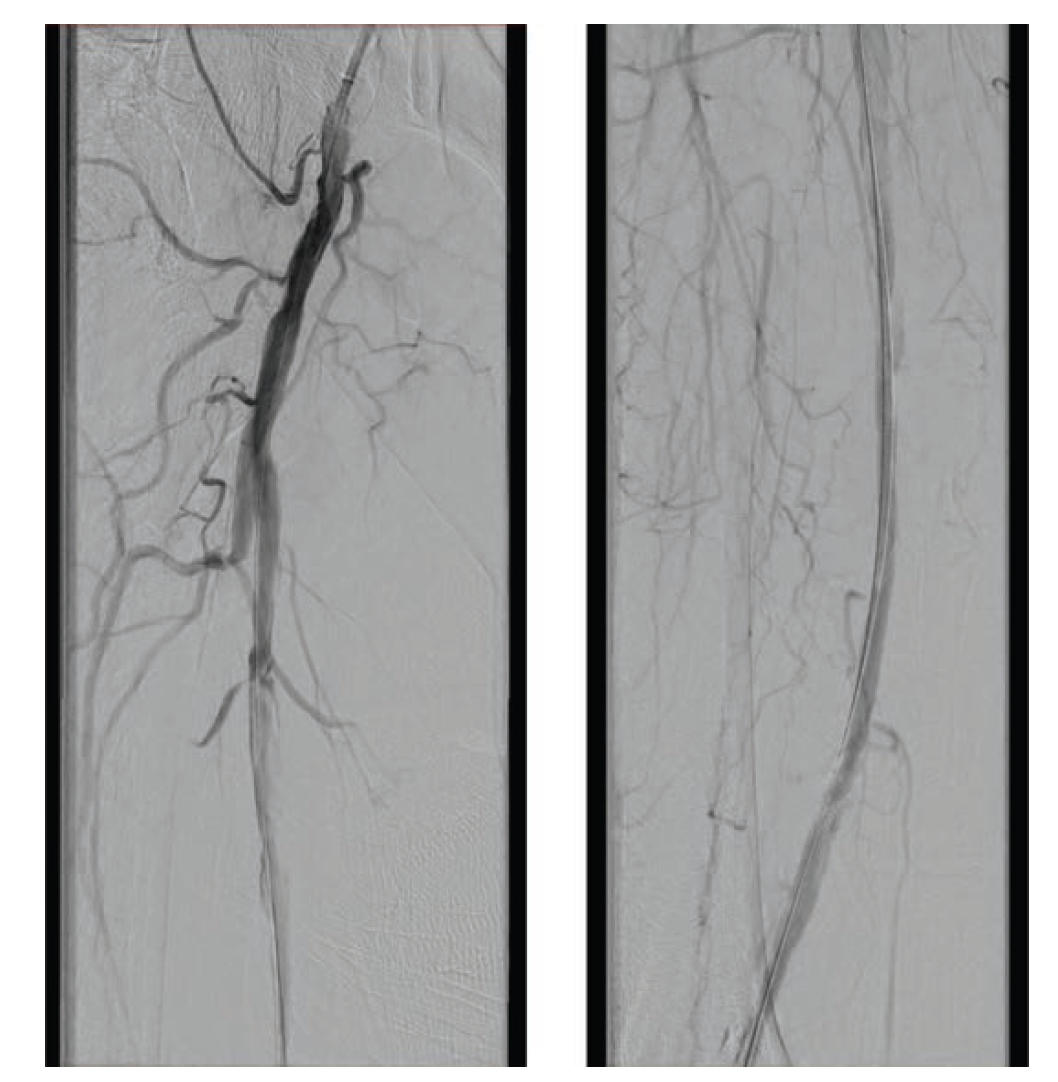

After the wire exchange, we attempted to aspirate, then flush, the 6F sheath with heparinized saline. After multiple failed attempts at sheath aspiration, we suspected a clotted arterial sheath and immediately proceeded to sheath exchange with a new 6F 45 cm sheath. Cautious to maintain wire position, the sheath was successfully exchanged. Saline flushing of the removed sheath resulted in expulsion of extensive clot burden (Figure 5). Repeat ACT confirmed therapeutic anticoagulation. The procedure concluded with percutaneous transluminal angioplasty followed by stenting of the SFA with BioMimics 6 x 150 mm stents (Figure 6). Final angiography demonstrated brisk flow through the SFA, popliteal, and anterior tibial arteries with no evidence of distal embolization (Figure 7 and Figure 8).